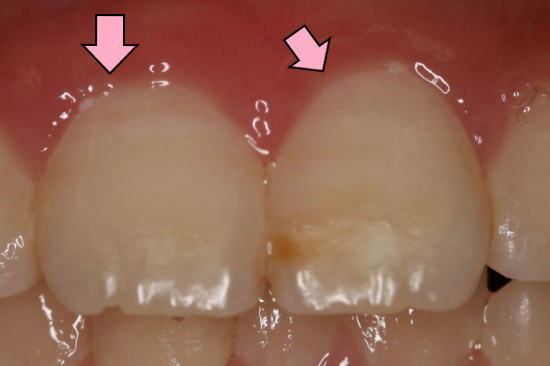

| 下記は緑の矢印の拡大 | 矢印の部分はむし歯が大きく元の状態には回復しませんでした。 | |